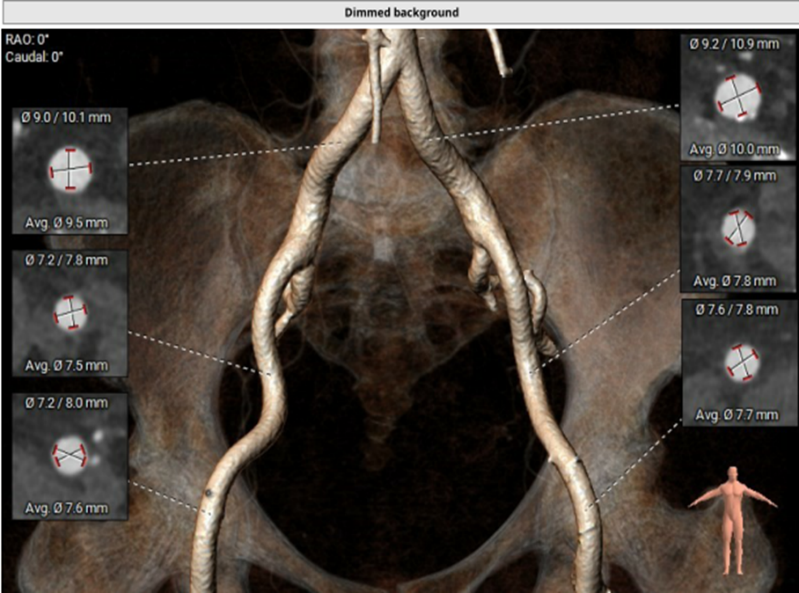

术前CT评估:

CT测量小结:

主动脉瓣为type -I 型二叶瓣,右无瓣叶嵴部融合伴有钙化并向窦部延伸16.0mm,瓣环平面可见钙化斑块向左室流出道延伸约12.3mm,瓣叶极重度钙化,中重度增厚;左冠窦较右无冠窦略偏大,右无冠窦基本等大;右冠脉开口高度可,左冠脉开口处可见瓣叶钙化斑块;心室大小可,室壁厚度可,中重度横位心;大血管走行自然,内径可,升主动脉扩张,主动脉弓部角度可,弓部、降主、腹主、左髂总动脉可见少-中量钙化斑块。